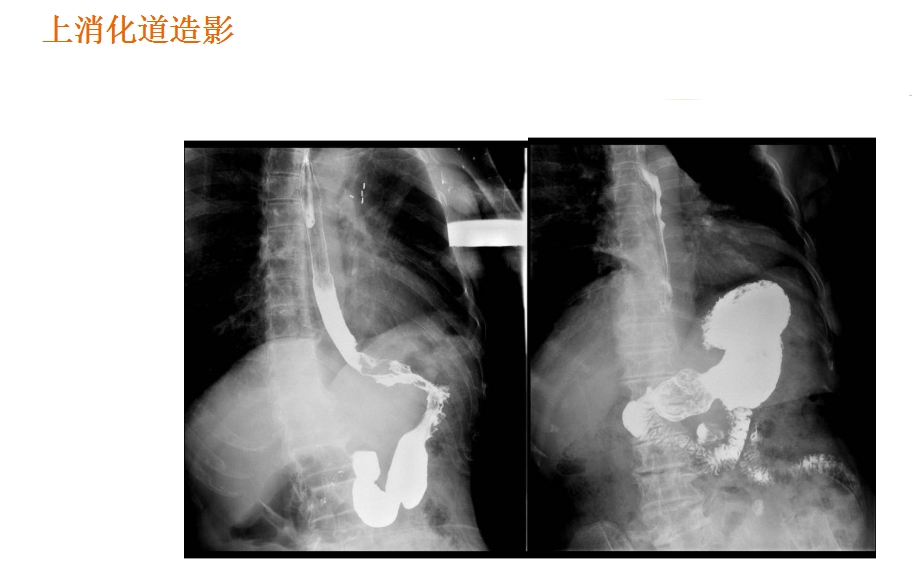

该设备属于多功能X线机,除具有传统数字胃肠机所有功能外,还有DR平板探测器X线摄影所有功能,主要用于消化道气钡双重对比造影、全脊柱拼接摄影、全下肢拼接摄影、ERCP、泌尿系造影、“T”管造影、钡剂灌肠、四肢造影、子宫输卵管造影等各类检查,是检查消化道溃疡、肿瘤、异物等疾病的主要方法之一。

在临床方面,强大的图像处理功能可以完成临床各种造影的需求。